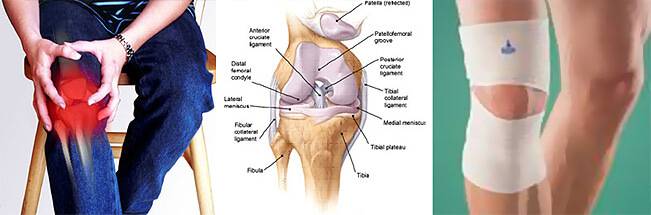

Заболевания и медицинские снимки: Жидкость в коленной чашечке

Раздел: Галерея прозрений